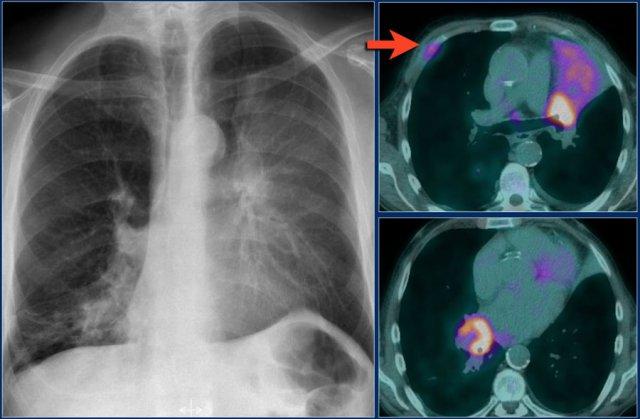

Xẹp thùy trên phổi phải

Hãy quan sát kỹ các hình ảnh trước, sau đó tiếp tục đọc.

Các dấu hiệu:

- Đám mờ hình tam giác

- Rốn phổi phải nâng cao

- Xóa mờ khoang sáng sau xương ức (mũi tên)

Trên PET-CT ghi nhận một khối u phổi kèm theo xẹp thùy trên phổi phải do tắc nghẽn phế quản thùy trên.

Một dấu hiệu thường gặp trong xẹp thùy trên phổi phải là hiện tượng ‘lều hóa’ cơ hoành (mũi tên xanh dương).

Bệnh nhân này có ung thư phổi vị trí trung tâm kèm di căn ở cả hai phổi (mũi tên đỏ).